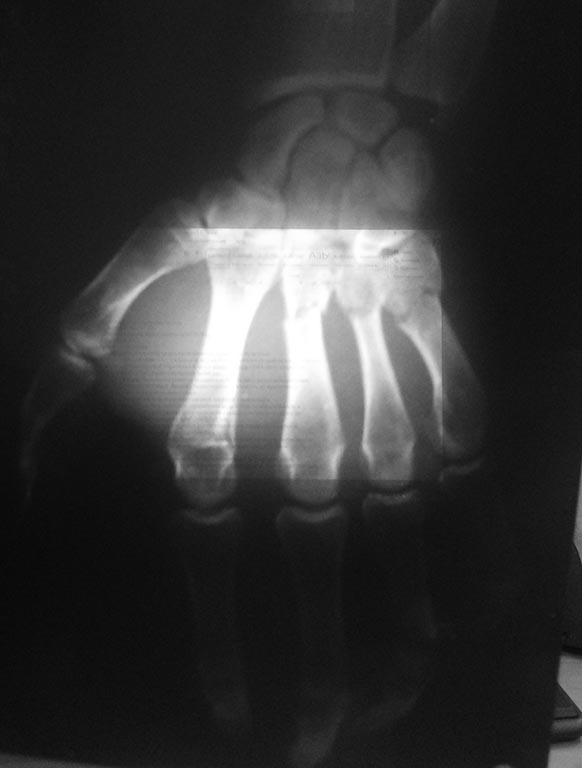

Перелом 2-пястных костей

Здравствуйте коллеги скажите , как провести спицы ?

Тактика лечение в данном случае? Открытый -закрытй

А почему перелом только двух пястных костей? А вторая проекция есть?

3 тоже, точно

2 может быть подголовчатый, себя бы конс полечил

Если патология ограничена той, что представлена на рентгенограмме, то я бы лечил консервативно.

Лучше никак не проводить, если в боковой проекции тожеприличное стояние.

Согласен. Вторая проекция - норма, тогда гипс

3,4,5 явно. 2-ая под вопросом. Косая проекция будет решающей.